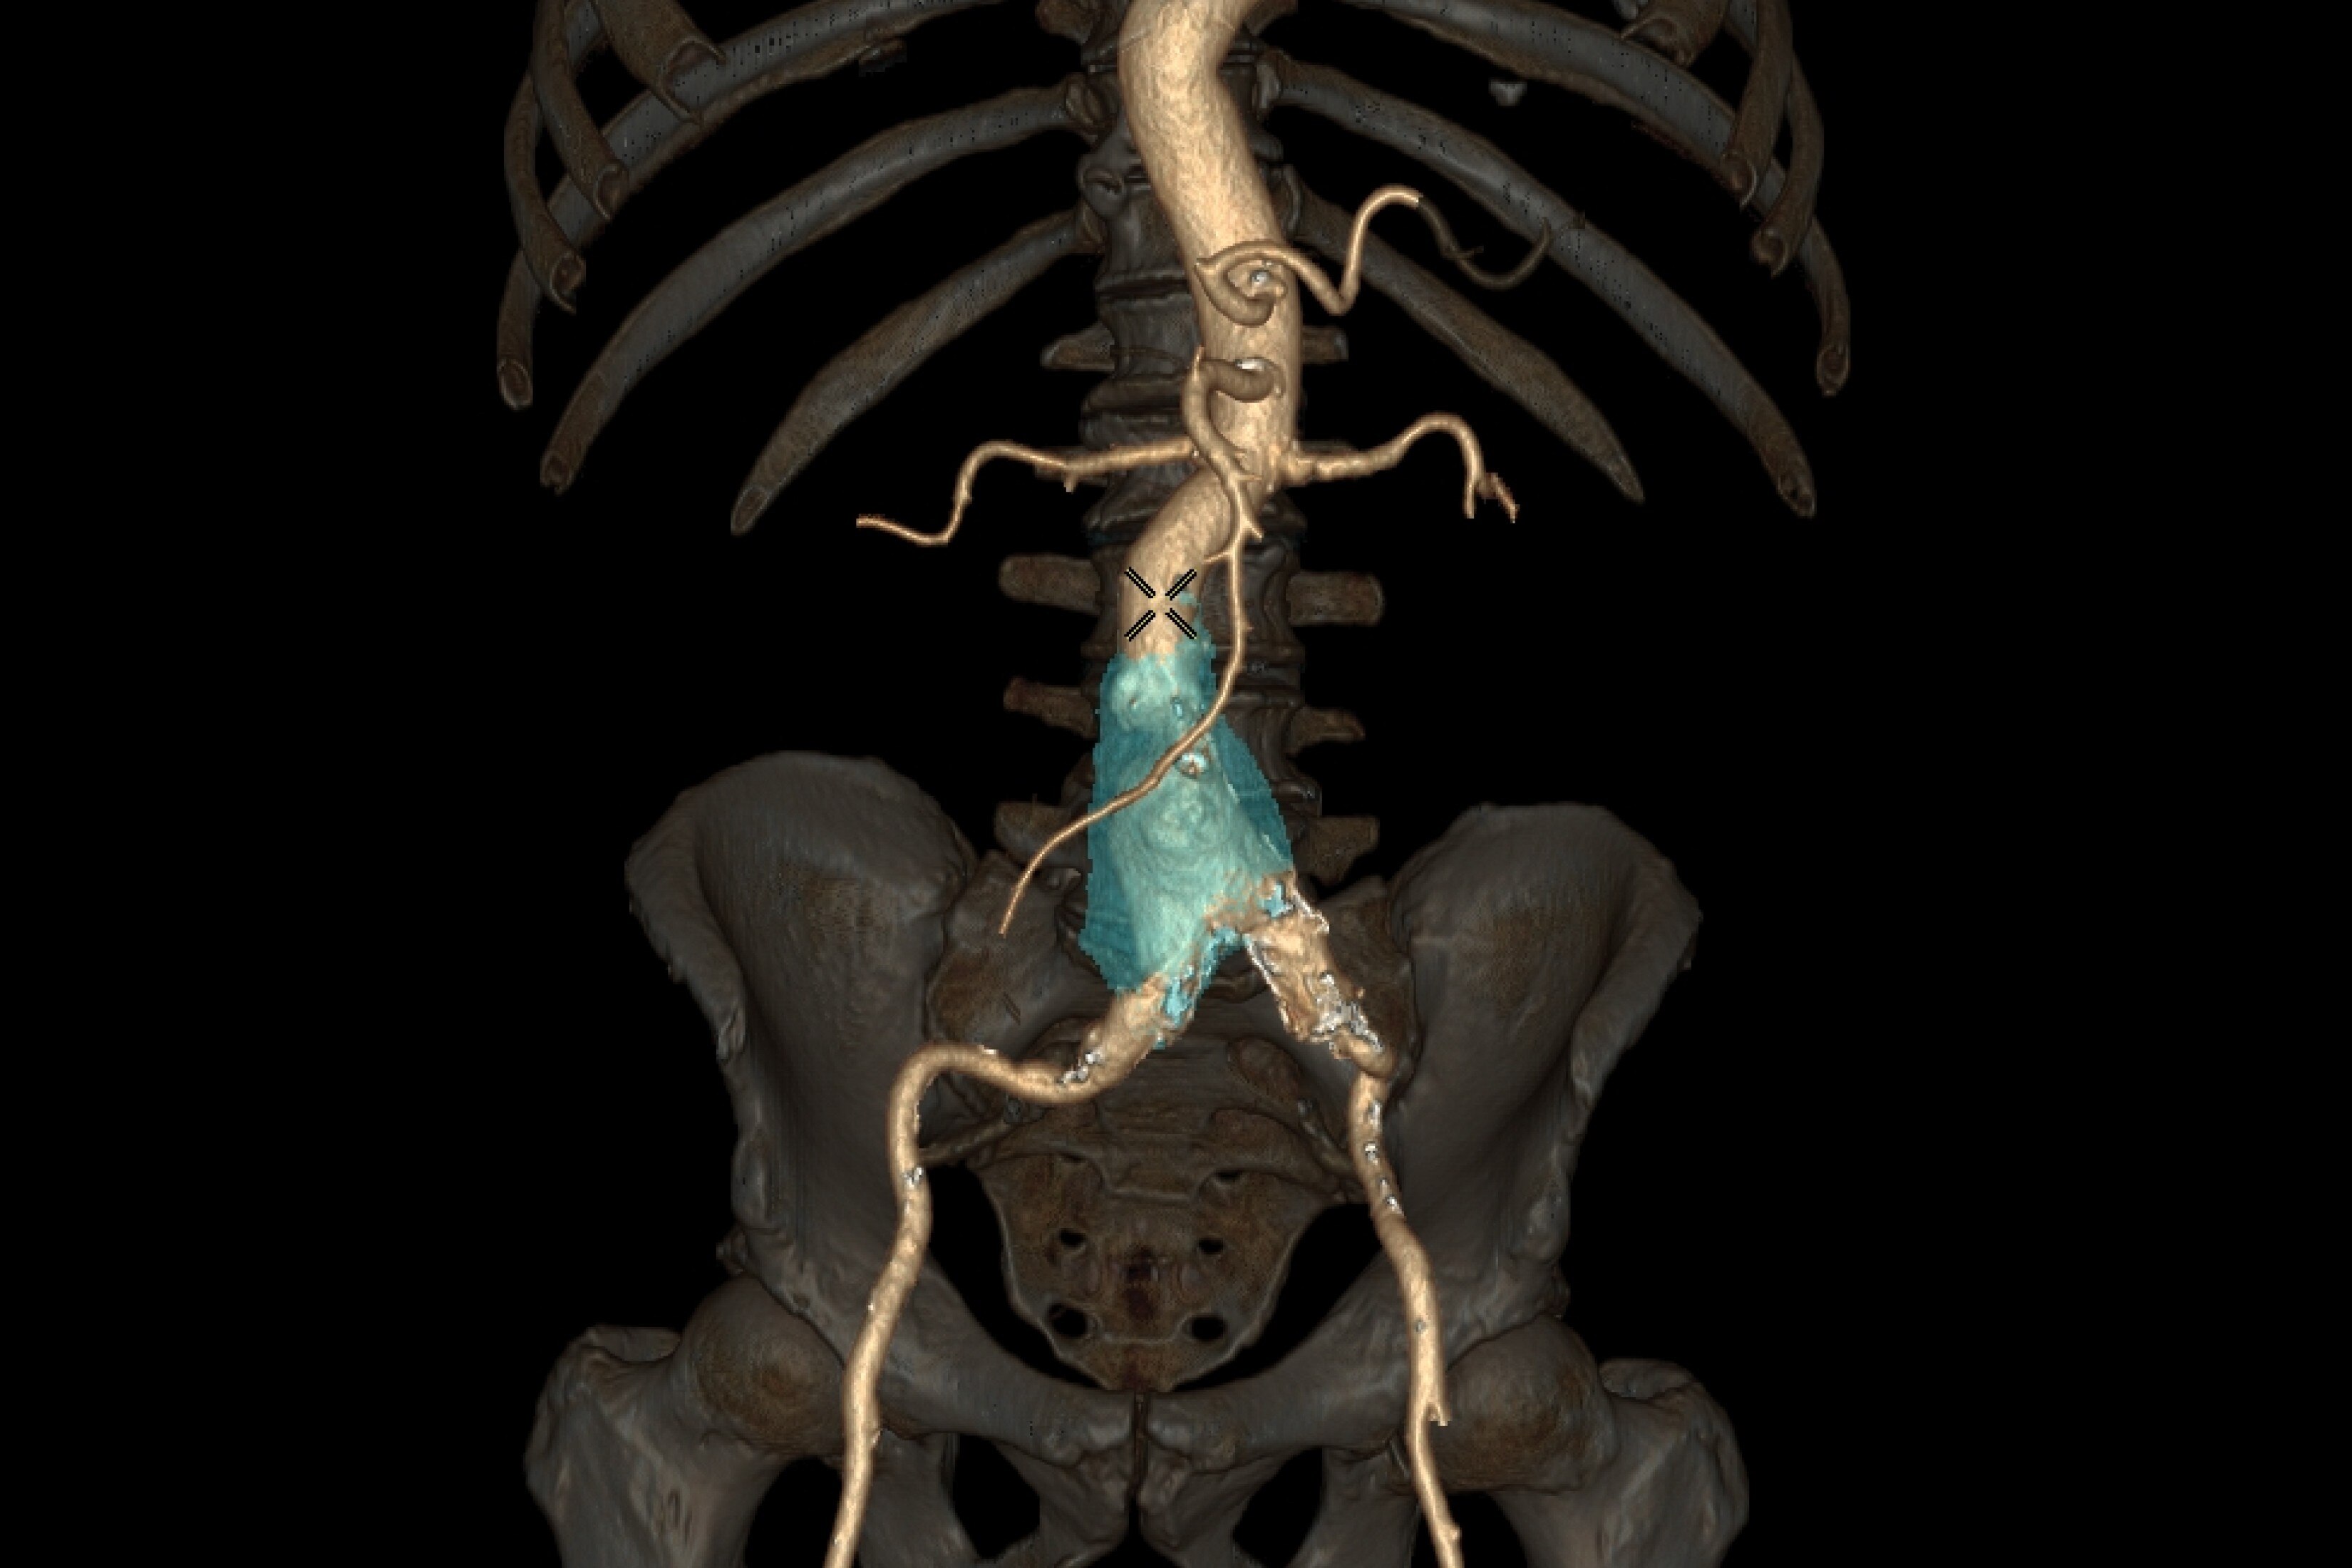

Automated detection of aorta and illiacs with auto-labeling of vessels

• Automated detection of aorta an illiacs with auto labeling of vessels.

• Thrombus detection with measurements and comparison over time.